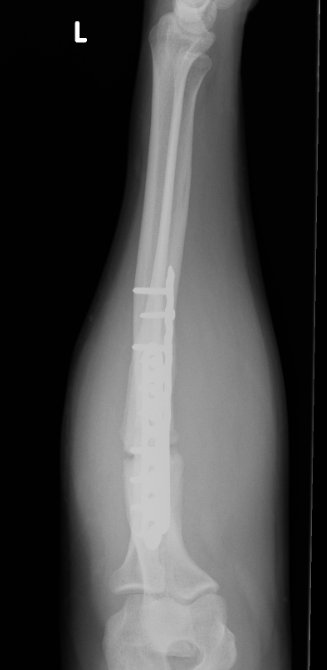

Options

Revision compression plating + drill intra-medullary canals + autograft

Results

- 35 forearm nonunions treated with revision compression plating and bone grafting

- average defect 2 cm

- 100% union